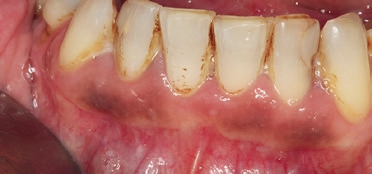

Die inhomogenen Leukoplakien sind mit einem deutlich höheren Entartungsrisiko verbunden [12]. Zu den inhomogenen Leukoplakien gehören die Leukoplakia verrucosa, die Leukoplakia erosiva und die noduläre Form [12]. Die Leukoplakia verrucosa erscheint als unruhige, warzige Läsion mit exophytischem Wachstum [12]. Die noduläre Form zeigt sich mit einer granulierenden oder knotigen Oberfläche [10]. Die erosive Leukoplakie imponiert durch rötliche Anteile in der Oberfläche (Abb. 2) und kann ein Hinweis auf eine eventuelle maligne Transformation sein [10,12,15,16].